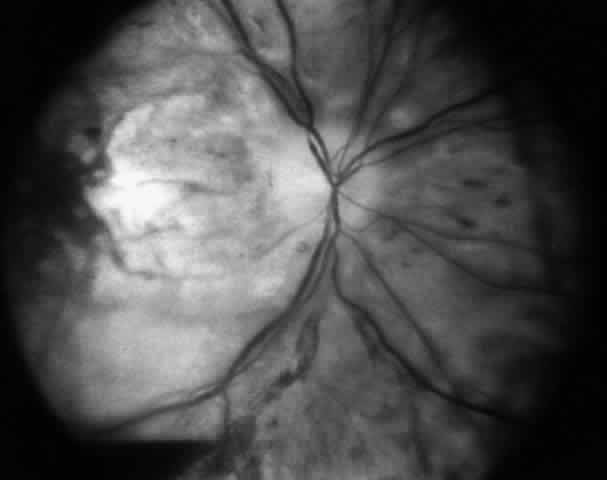

Fig. 6. Loss of vision after strabismus surgery is very uncommon. This 45-year-old woman had received orbital radiation prior to her strabismus surgery. The surgery was performed with retrobulbar anesthesia. Four days after the operation, vision was decreased from 20/20 to light perception. It is presumed that there was injection of the anesthetic into or around the optic nerve that caused compromise of the central retinal artery. The fundus photograph was taken 4 days after the procedure.